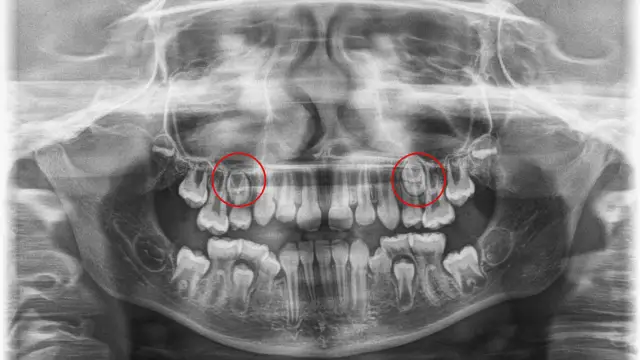

Brak zawiązków zębów stałych u dziecka – co robić, aby pomóc?

Brak zawiązków zębów stałych u dziecka? Dowiedz się, co robić, aby pomóc swojemu dziecku w tej trudnej sytuacji i jakie są dostępne opcje leczenia.